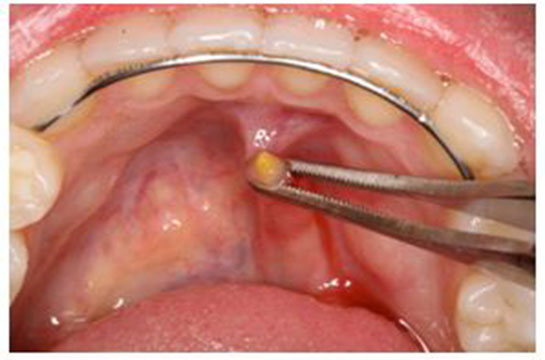

Rahim Biyopsi Nedir?Rahim biyopsisi, rahim dokusunun bir örneğinin alınarak mikroskop altında incelenmesi işlemi olarak tanımlanabilir. Bu işlem, rahim kanseri, endometriozis, myomlar, polipler ve diğer rahim hastalıklarının teşhisinde önemli bir rol oynamaktadır. Rahim biyopsisi, genellikle jinekolojik muayene sırasında veya özel durumlarda cerrahi bir işlemle gerçekleştirilir. Rahim Biyopsisi TürleriRahim biyopsisi, çeşitli yöntemlerle yapılabilir. Bu yöntemler şunlardır:

Her bir biyopsi türü, farklı durumlar için uygun olup, doktorun önerisine göre seçilir. Rahim Biyopsisi Nasıl Yapılır? Rahim biyopsisi, genellikle birkaç aşamadan oluşur: